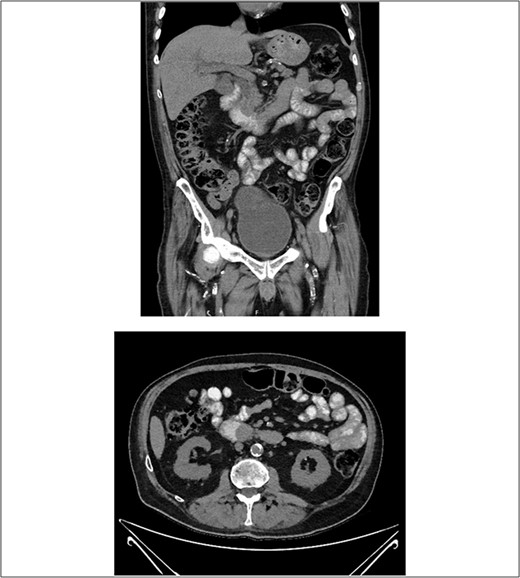

A computed tomography (CT) with oral contrast of the patient’s abdomen and pelvis revealed a soft tissue ampullary lesion projecting into the duodenal lumen and resultant dilatation of the CBD and intrahepatic ducts. Adequate assessment of lesion was limited by the lack of IV contrast in the context of the patients AKI. Additionally, the periportal, intraabdominal and epicardial lymph nodes were mildly prominent (Fig. 1).

CT with oral contrast revealing a soft tissue ampullary lesion on axial and coronal images.